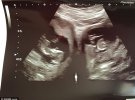

Англійка Дженіфер Ештвуд із Камборна, графство Корнуолл, народила двійнят з двох різних маток.

Ймовірність такої події складає 500 млн до одного. Історія людства знає менше 100 зафіксованих випадків народження таких дітей. Всього кілька з них проживає у Великобританії, повідомляє Dailymail.

Більшість вагітних з діагнозом "бікорнуальна матка", мають одну дитину в одній матці. Так і сталося з першою дитиною - 8-річною Міллі.

"Я народила одну дитину і це було просто. Тепер моє тіло мене здивувало. Ми дізналися про вагітності на 20-тижневому сканері. З того часу всі говорять яка це надзвичайна рідкість", - каже Дженіфер.

Пара дізналася про поповнення в грудні. Аномалія не викликає додаткових проблем із зачаттям, але збільшується ризик викидня або передчасних пологів.

На 34 тижні через кесарів розтин народилися Піран та Поппі. Вони приїхали додому через два тижні після лікування жовтянки.

"Я гадала, що знаю своє тіло досконало. Дві матки явище рідкісне саме по собі, але щоб дві різні яйцеклітини запліднилися в один час і були в правильному місці... Це чудо", - каже вона.